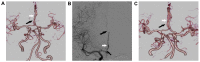

Figure 2.

(A) CT angiography on day 5 after onset showed severe stenosis at the origin of the A2 segment (black arrow) with distal dilatation (white arrow) and occlusion at the origin of A3 segment of the right ACA. (B) Digital subtraction angiography on day 6 also showed severe stenosis at the origin of the A2 segment (black arrow) with distal dilatation (white arrow) and occlusion at the origin of the A3 segment of the right ACA (black arrow). (C) CT angiography after 5 months showed that the stenosis of A2 segment was considerably improved (black arrow) and the dilatation of A2 segment had almost disappeared (white arrow). CT, computed tomography; ACA, anterior cerebral artery.